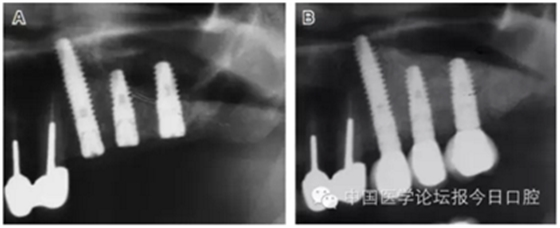

病例5 多顆種植體(圖7)

圖7